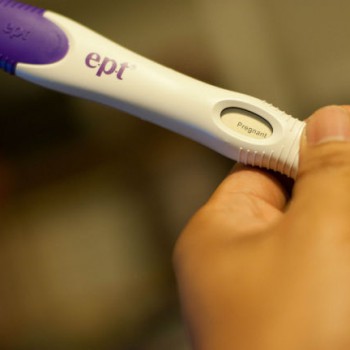

The decision to have an abortion can be hard choice. But we believe that all women have a right to choose. Every woman that feels an abortion is in her or her family’s interests, should have access to safe abortion as well as to advice.

We offer affordable prices to enable more women to access our services. We are aware that most patients may be under strenuous financial constraints and yet desire to terminate. Therefore, we make it a point to charge our clients fairly. We offer a 50% discount for students considering the fact that they are not working and do not have considerable means to acquire money.

Very safe. Our doctors are gynecologists who have years of experience specializing in abortion care. It’s unusual to have even minor problems.

Having a child should be a choice. You should not be forced into child birth when you are a child yourself, if your finances do not allow, if you do not have a committed partner or any other reason unique to you. Having and looking after a child is very serious business that you should only and only join if you are ready.

Do you want to terminate? Call us Today

Our Contact Details are on the right of your computer screen get hold of us today for an affordable,

non-judgmental, safe and private abortion.